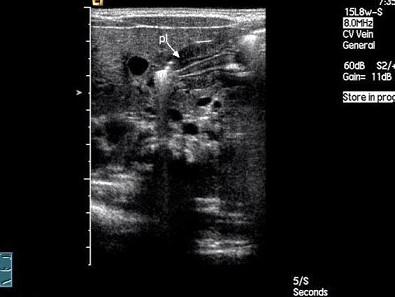

问题 患儿,出生3周,食欲旺盛,吮奶急,但几乎每次喂奶后立即或不久即吐,呈喷射状。X光钡餐检查,见胃窦与幽门管近端连接处呈喙状突出阴影称鸟喙征。超声检查如图,最可能的诊断是?(?)

选项 A.幽门狭窄 B.胃食管返流 C.胃溃疡 D.食管裂孔疝 E.肠套叠

答案 A